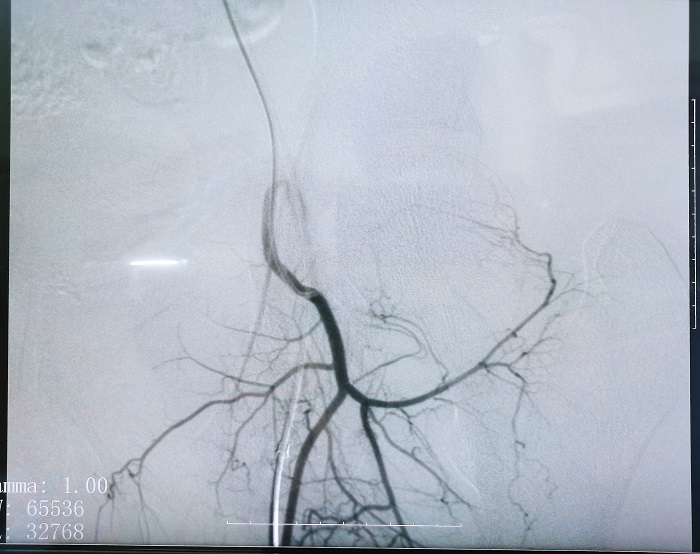

米兰网页版登录入口平板介入中C在FTE手术过程中拍摄的造影图像

若根据HSG的诊断,患者存在输卵管积水,则可行输卵管栓塞术(Fallopian tube embolization, FTE),通过介入手段,注入栓塞剂或使用弹簧圈等器材进行栓塞,可以有效地阻断输卵管内的血流和组织,从而治疗输卵管积水。这个过程通常是在X线或超声引导下进行的,可以清楚地看到输卵管的情况。

SSG是一种常用的检查输卵管是否通畅的方法,通过造影剂显影来观察输卵管的形态和通畅情况。SSG适用于评估输卵管是否通畅,常用于不孕症患者的初步检查。如显影,再加压注入混合药液,利用液体静压力的推动作用,使输卵管得以通畅。若输卵管未显影,则行FTR,在X线或超声引导下,医生将导管插入输卵管中,通过导管注入特殊的药物或器械,以清除堵塞物、分离粘连并疏通输卵管。如果疏通成功,再注入造影剂和混合液通过HSG来观察输卵管的通畅情况。